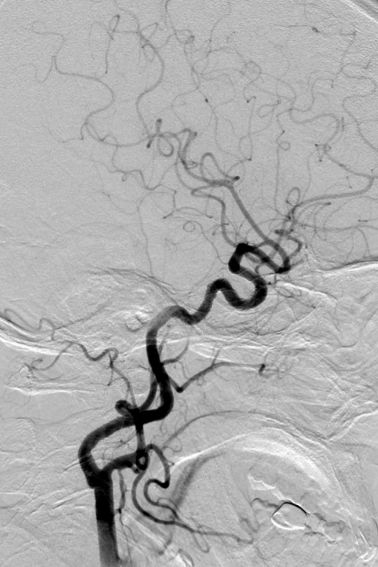

Tubridge®血管重建装置专用支架导管T-track到位,引入4.0mm*30mm支架。

准确定位后,锚定支架头端,缓慢推送支架的同时控制支架张力,顺利释放支架。

为进一步确保Tubridge®血管重建装置完美贴壁,上J型导丝支架内“按摩”。

多角度确认支架已完全贴壁。

正侧位造影示动脉瘤内造影剂明显滞留,载瘤动脉通畅,血流导向作用显著。

术后6个月复查动脉瘤完全闭塞,局部血管重建。